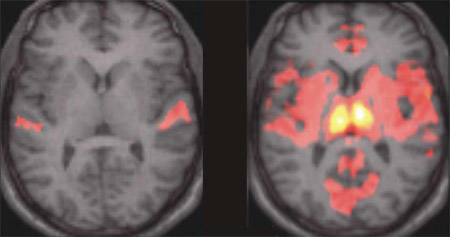

Bild: MPI für Psychiatrie